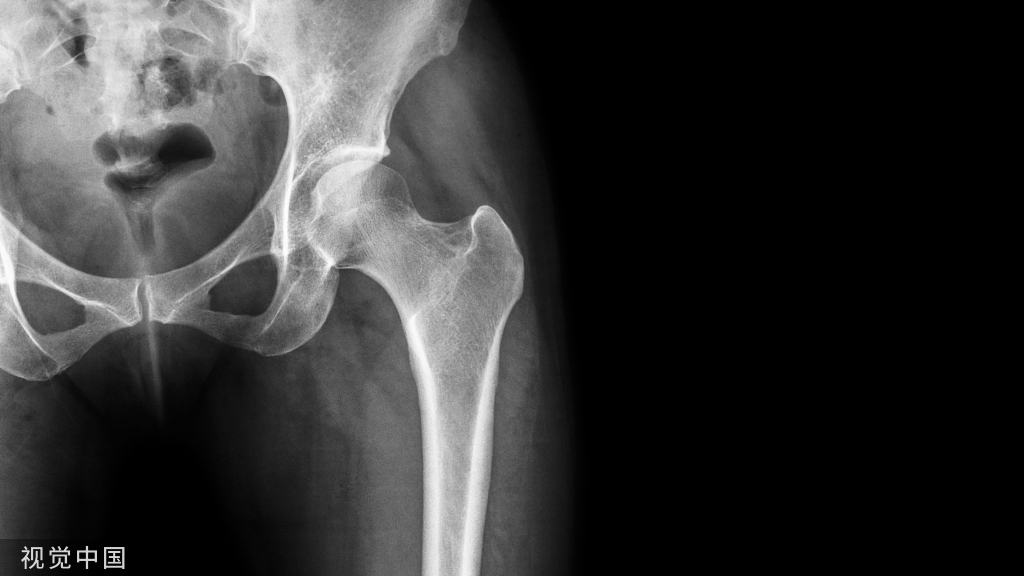

本研究通过研究C臂X线透视下经皮腰椎椎弓根螺钉置入合适的入钉点的特点和规律,旨在提高经皮椎弓根螺钉置入的准确性,减少近端关节突关节侵犯的发生率。

2.研究C臂X线片上进钉点、椎弓根投影与近端关节突关节之间的关系。观察不同腰椎节段椎弓根的投影形态,同时研究椎弓根投影外缘与头端关节突外缘的关系。

1.椎弓根投影形态:L1 - L3呈椭圆形,L4 - L5呈圆形;

2.C臂检查显示,关节突外缘位于椎弓根投影外缘外侧,与椎弓根投影不重叠;